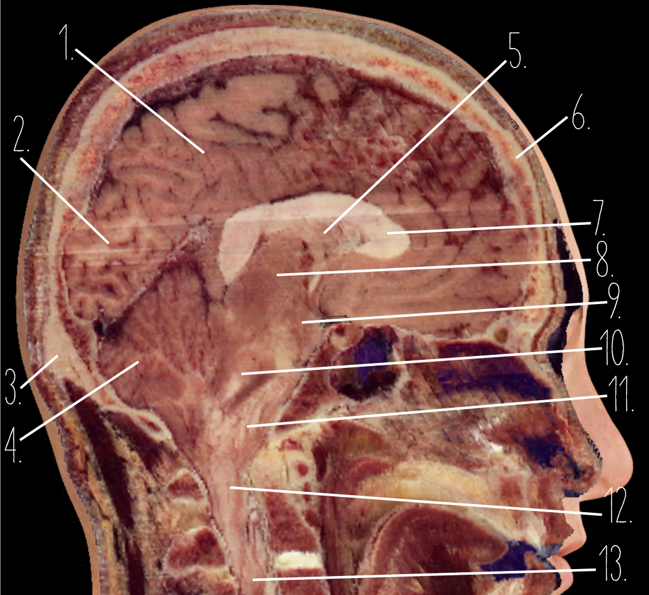

Brain Cross Sectional

1

Frontal Bone

2

Frontal Lobe

3?

Falx Cerebri

4?

Gray Matter

5?

White Matter

6?

Sulcus

7?

Gyrus

8?

Fissure

1?

Parietal Lobe

2?

Cerebellum

3?

Occipital Bone

4?

Cerebellum

5?

Lateral Ventricle

6?

Frontal Bone

7?

Corpus Callosum

8?

Thalamus

9?

Hypothalamus

10?

Midbrain

11?

Pons

12?

Medulla Oblongata

13?

Spinal Cord